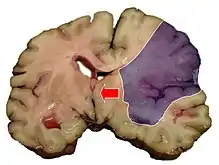

This subdural hematoma/epidural hematoma (arrows) is causing midline shift of the brain

Midline shift measurements and imaging has multiple applications. The severity of brain damage is determined by the magnitude of the change in symmetry. Another use is secondary screening to determine deviations in brain trauma at different times after a traumatic injury as well as initial shifts immediately after.[3] The severity of shift is directly proportional to the likeliness of surgery having to be performed. The degree of MLS can also be used to diagnose the pathology that caused it. The MLS measurement can be used to successfully distinguish between a variety of intracranial conditions including acute subdural hematoma,[5][7] malignant middle cerebral artery infarction,[3] epidural hematoma, subarachnoid hemorrhage, chronic subdural hematoma, infarction, intraventrical hemorrhage, a combination of these symptoms, or the absence of pertinent damage altogether.[7]